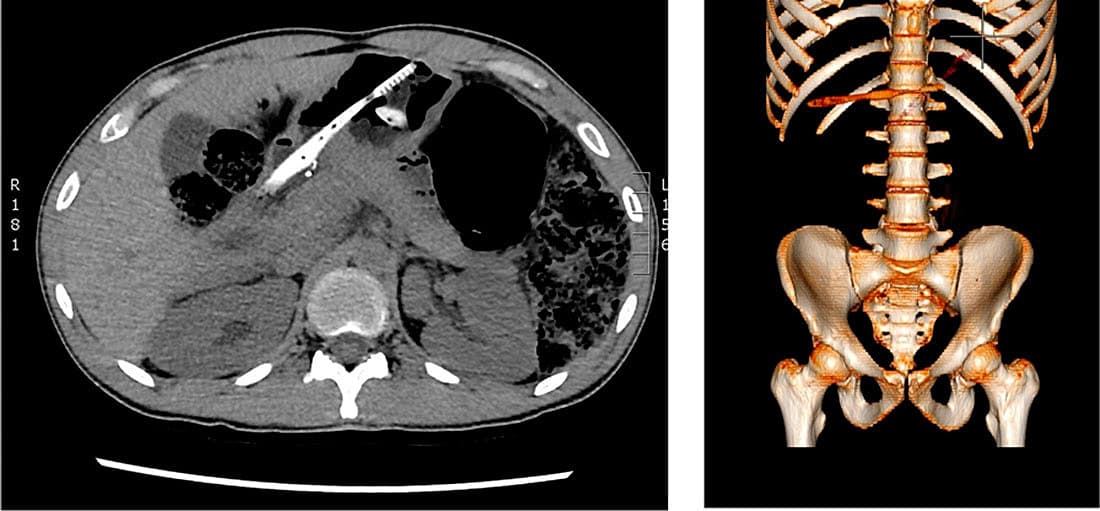

En 27-årig mand med skizofreni blev henvist til skadestuen pga. langvarige mavesmerter. En ultralydskanning viste et fremmedlegeme (FL) i ventriklen. En CT viste to tandbørster i ventriklen. Efterfølgende blev disse fjernet med endoskop. FL i ventriklen forekommer hyppigst hos børn fra et halvt til seks år. Hos voksne ser man tit FL hos psykisk syge. Typiske symptomer kan være irritabilitet, dysfagi, savlen, opkastning og retrosternal smerte. CT bør overvejes ved mistanke om multiple FL, perforation, absces eller ileus. Kontrastrøntgenoptagelse anbefales ikke pga. risiko for aspiration [1]. De fleste FL passerer spontant gennem gastrointestinalkanalen. Konservativ

behandling anvendes generelt hos asymptomatiske patienter med et lille stumt FL i ventrikel [1]. Ved store (> 5 × 2 cm) og skarpe FL i ventriklen anbefales endoskopisk fjernelse.